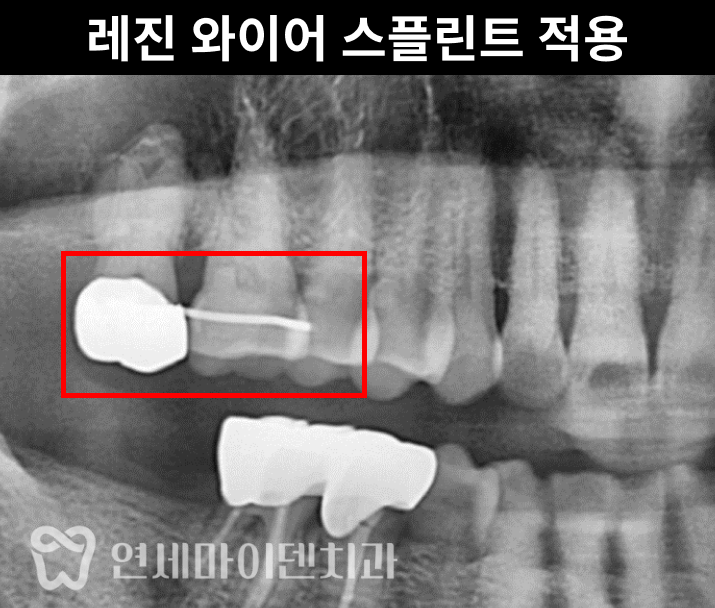

② 레진 와이어 스플린트 적용

상대 교합 관계를 유지하기 위해 레진 와이어 스플린트를 적용했습니다.

이는 윗쪽 어금니가 아래로 내려오는 ‘대합치 정출’을 예방하고,

임플란트 후에도 교합의 균형을 유지하며

음식물이 끼는 문제를 최소화할 수 있습니다.맨 끝 어금니 임플란트, 꼭 해야할까?